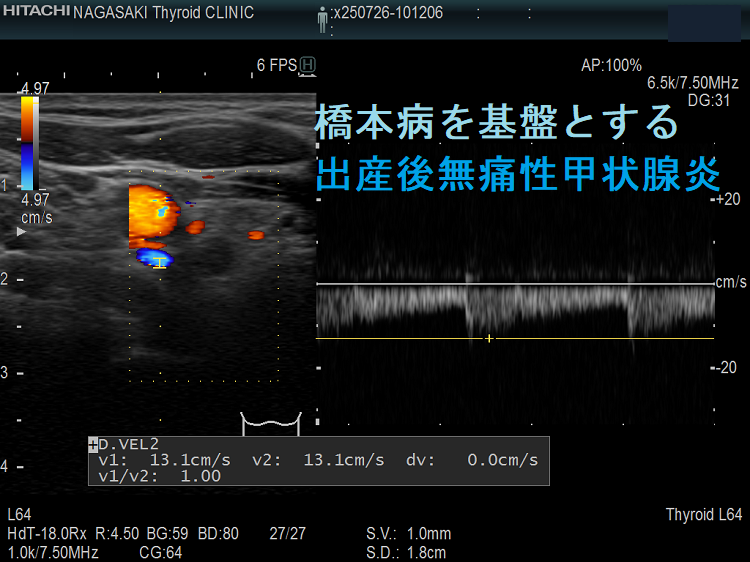

出産後無痛性甲状腺炎 超音波(エコー)画像;下甲状腺動脈の収縮期最大血流速度(ITA-PSV)

無痛性甲状腺炎であるため、下甲状腺動脈の収縮期最大血流速度(ITA-PSV)は低値です。

橋本病を基盤とする出産後無痛性甲状腺炎(水平断) ドプラーモード;無痛性甲状腺炎であるため、内部血流は少ない。

橋本病を基盤とする出産後無痛性甲状腺炎下甲状腺動脈の収縮期最大血流速度(ITA-PSV);無痛性甲状腺炎であるため、下甲状腺動脈の収縮期最大血流速度(ITA-PSV)は低値